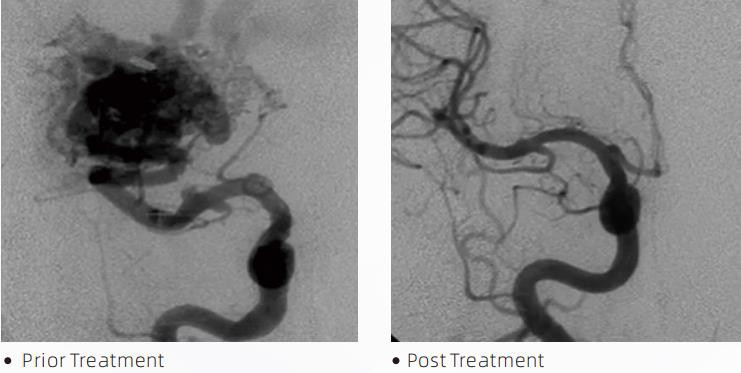

लावाटीएमलिक्विड एम्बोलिक सिस्टम सेरेब्रोवास्कुलर विकृतियों के इलाज के लिए एक इंटरवेंशनल एंडोवास्कुलर थेरेपी है। सेरेब्रोवास्कुलर विकृति सौम्य या घातक न्यूरोवास्कुलर असामान्यताओं के एक समूह को संदर्भित करती है जो इंट्राक्रैनील रक्तस्राव, सेरेब्रल रोधगलन, सेरेब्रल इस्किमिया और अन्य बीमारियों का कारण बन सकती है। लिक्विड एम्बोलिज़ेशन सिस्टम एक चिकित्सा उपकरण है जिसे सरल इंट्रावास्कुलर सम्मिलन के माध्यम से प्रशासित किया जाता है, जो एक विशेष तरल पदार्थ को इंजेक्ट करके असामान्य मस्तिष्क रक्त वाहिकाओं को एम्बोलाइज़ करता है। द्रव पदार्थ रक्त वाहिकाओं के भीतर एक नियंत्रित ऊतक एम्बोलिज्म बनाता है, जो रोगियों पर सेरेब्रोवास्कुलर विकृतियों के प्रभाव को कम कर सकता है। एक डीएमएसओ संगत डिलीवरी माइक्रो कैथेटर जिसे न्यूरोवास्कुलचर में उपयोग के लिए संकेत दिया गया है, एम्बोलिज़ेशन साइट तक पहुंचने के लिए उपयोग किया जाता है। लावा लिक्विड एम्बोलिक एजेंट एक गैर-चिपकने वाला तरल एम्बोलिक एजेंट सिस्टम है जिसमें डीएमएसओ (डाइमिथाइल सल्फ़ोक्साइड) में घुले ईवीओएच (एथिलीन विनाइल अल्कोहल) कोपोलिमर और फ्लोरोस्कोपी के तहत दृश्य के लिए कंट्रास्ट प्रदान करने के लिए निलंबित माइक्रोनाइज्ड टैंटलम पाउडर शामिल है। लावाटीएमतीन उत्पाद फॉर्मूलेशन में उपलब्ध है, LAVA-12, LAVA{1}} और LAVA-34। लावा-12: दूरस्थ सूक्ष्म वाहिकाओं और छोटे फीडरों के माध्यम से भोजन खिलाते समय अनुशंसित। लावा-18: पेडिकल इंजेक्शन खिलाते समय निडस के करीब लगाने की सलाह दी जाती है; लावा-34: उच्च प्रवाह और बड़े फिस्टुलस घटकों को एम्बोलाइज़ करने के लिए अनुशंसित।